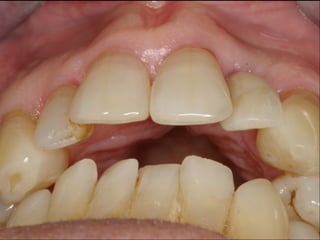

This document discusses several dental implant cases where porcelain crowns were used to restore teeth. It describes the process for each case, including placing implants, attaching provisional crowns, modifying the crowns, adding porcelain, and delivering the final restoration. Photos show before and after images for each case, which include replacing premolar teeth, bridges, and full upper dental arches.